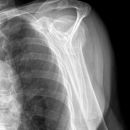

Fraktur Coracoid und Ala scapulae